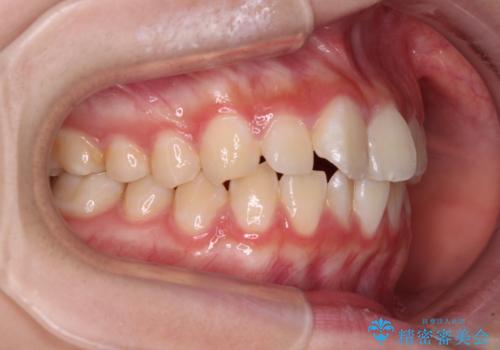

- 上下前歯のねじれを気にして来院された患者様です。

ワイヤー矯正でもマウスピース矯正でも対応可能でしたが、マウスピース矯正の自己管理が面倒であること、上顎前歯の捻転が著しいことから、ワイヤー矯正での治療を希望されました。